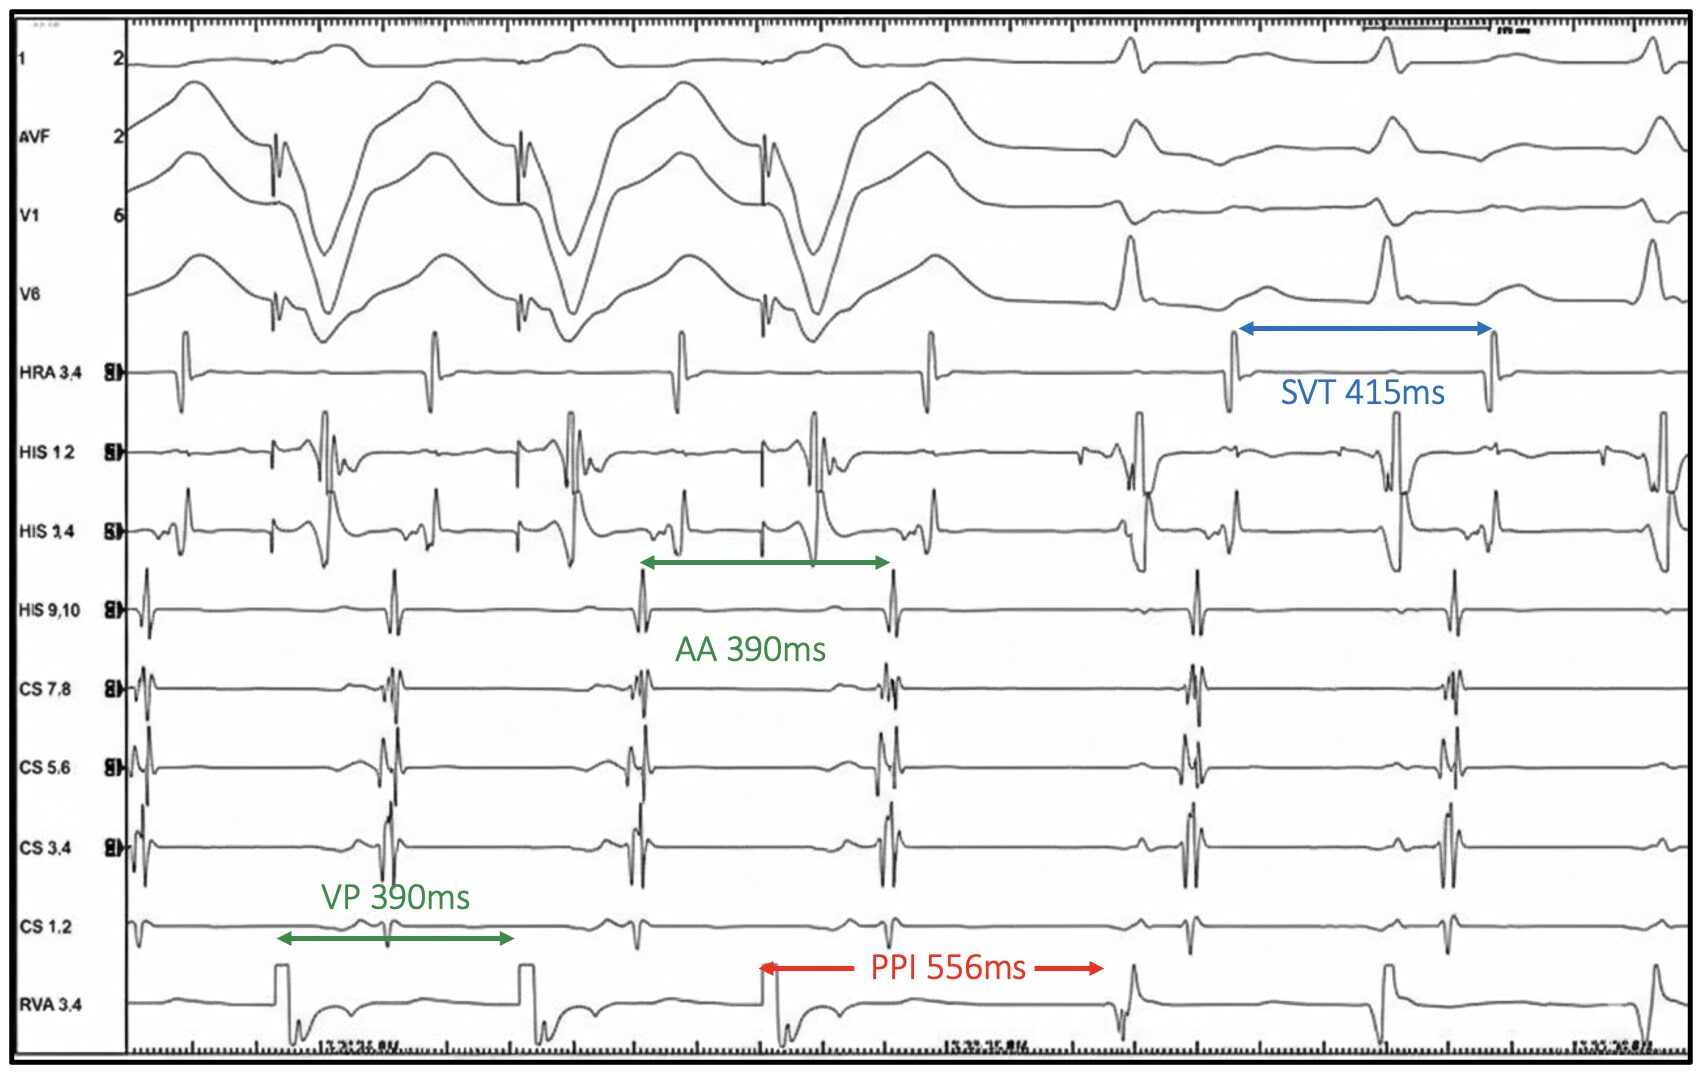

Let us examine the EGM above

The intrinsic tachycardia demonstrates:

- Narrow QRS

- 1:1 AV relationship

- A His preceding each QRS

Antidromic AVRT and VT can therefore be excluded. The atrial activation pattern will be revisited shortly.

VODP is delivered at 390ms, approximately 25ms faster than the tachycardia cycle length (TCL 415ms).

Was entrainment achieved?

Yes. The atria have been accelerated to the pacing cycle length and tachycardia persists following pacing.

PPI = 556ms, TCL = 415ms

PPI–TCL = 141ms

A PPI – TCL of 141ms would suggest AVNRT in this case. But interpretation should not stop here. See the EGM below with additional callipers.